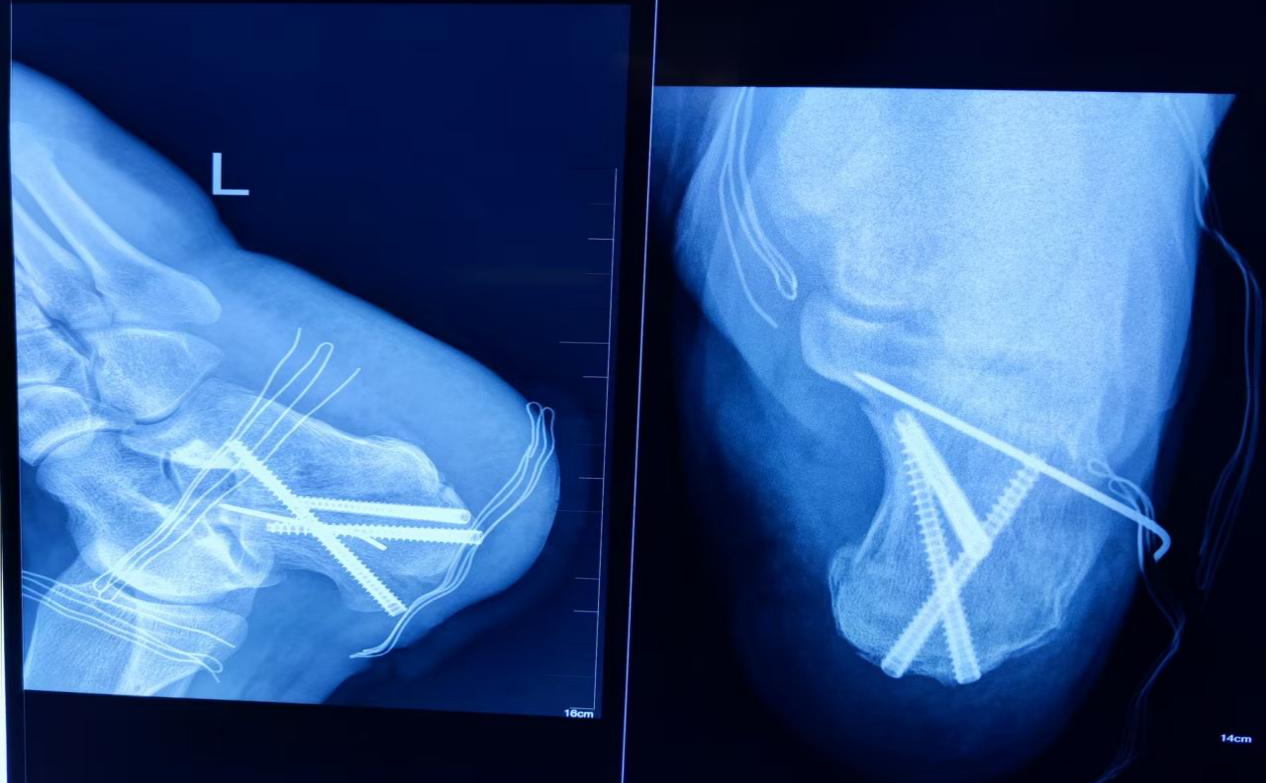

术后DR影像

术后,科室医护团队为患者开展抗炎、消肿、切口护理等规范化治疗,早期介入足踝功能锻炼指导。患者切口愈合理想,疗效获患者及家属高度认可。

据了解,相较于传统切开复位内固定术,该微创技术(跟骨骨折完全闭合复位下微创空心螺钉内固定术)优势显著:大幅降低切口感染、皮肤坏死、钢板外露等并发症风险;不受肿胀及皮肤软组织条件限制,可早期手术,缩短术前等待时间;减少住院费用与住院时长;支持患者早期功能锻炼,加速康复,实现患者获益最大化。